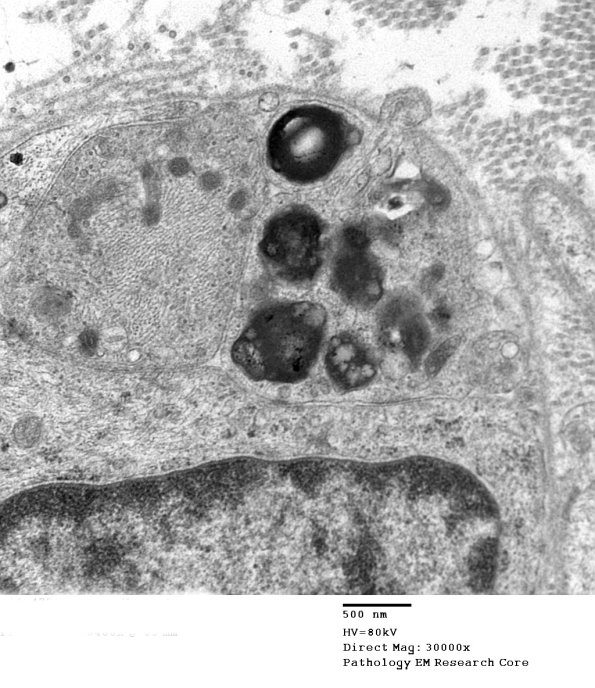

Higher magnification of image #2F5A. (electron micrograph)